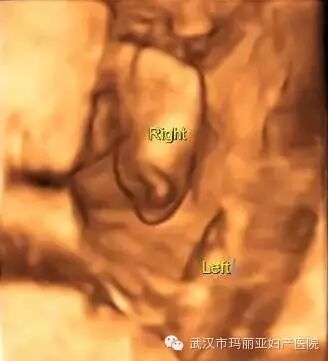

武汉玛丽亚妇产医院引进的世界领先的美国GE-E8四维彩超设备室目前世界上最先进、分辨率最高的彩色超声设备,具有即时立体成像、清晰准确的特点。

它能够多方位、多角度地观察宫内胎儿的生长发育情况,为早期诊断胎儿先天性体表畸形和发育异常提供科学依据。还能对胎儿的体表进行检查,如唇裂、脊柱裂、大脑、肾、 骨骼发育不良等,以便尽早的进行治疗。